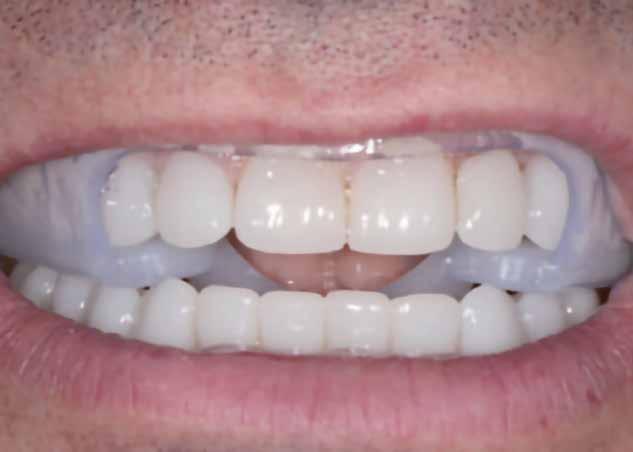

A fogszabályzó kezelések egyik legfontosabb célja, hogy elérjük a lehető legharmonikusabb interokkluzális fogérintkezéseket, továbbá az állcsont relációs helyzetének frontális és szaggitális síkban is megfelelőnek kell lennie. A fogszabályzás befejezésekor a fogpozícióknak nem orthodonciai, hanem protetikai szempontok szerint kell ideálisnak lenniük. Az Invisalign ClinCheck szoftver (Align Technology) segítségével a protetikus az orthodontussal együtt meg tudja határozni azokat a végső fogpozíciókat, amelyek a lehető legjobb végeredmény biztosításához elengedhetetlenek. Bizonyos klinikai paramétereket, mint a fogak klinikai koronájának nagyságát, az egyes fogak fogíven belüli optimális pozícióját, a fogívek egymáshoz viszonyított helyzetét, a fogak között látható rések nagyságát, a frontfogak tengelyének dőlését, az overjet és overbite mértékét már a kezelések megkezdése előtt pontosan definiálni kell. Ezeket az adatokat viszont csak a tervezett végleges fogpótlás ismeretében lehet meghatározni, ezért van szükség az orthodontus és a protetikus szoros együttműködésére.

A közös munka során az egyik legelső és legfontosabb feladat annak a meghatározása, hogy a páciens jelenlegi maximális interkuszpidációs helyzete (IKP) milyen mértékben tér el az

32 e-Journal DENTAL HÍREK

33 VII. ÉVFOLYAM – 2024. 3. SZÁM

1-4. ábra: Kiindulási állapot. 5. ábra: ClinCheck szoftverrel történő kiértékelés. A kiindulási és az orthodonciai kezelés végén elérni kívánt állapot összehasonlítása. 6-9. ábra: Az orthodonciai kezelés végén elért állapot.

10. a-c. ábra: Módosult passzív erupció jelenlétének diagnosztizálása radiológiai felvételek segítségével (altered eruption radiographic technique; AlteRx).

11. a-b. ábra: A gingivectomia és frenulectomia elvégzését követően látható állapot.

12. a-d. ábra: Az állcsont relációs helyzetét a helyreállítás befejezése után elérni kívánt állapotot bemutató mock-up felhelyezését követően rögzítettük az arcív és a harapási sánc segítségével.

állcsontok centrális relációs helyzetétől (CR). Ezt a helyzetet úgy is leírhatnánk, mint az a legideálisabb állkapocs-ízületi helyzet, amely elérését követően a lehető legkedvezőbb állkapocshelyzetből történhet meg az alsó és felső fogív végleges fogpótlásokkal történő helyreállítása. Ennek a meghatározásakor a frontális és a szaggitális síkban megfigyelhető komponenseket is figyelembe kell venni. Az optimális állcsont relációs helyzetének megállapítása előtt elengedhetetlen az állkapocs-ízület beprogramozása, a rágóizmok lazítása, és

állkapocs-ízületi rendellenességek fennállásának ellenőrzése. Amennyiben állkapocs-ízületi rendellenességeket diagnosztizálunk, úgy először gnatológiai terápiát alkalmazunk, melynek célja a rágóizmok működésének és az állkapocs-ízület egészségének helyreállítása. A komplex rehabilitációs beavatkozások kivitelezésének megtervezését csupán az új, biológiai és funkcionális szempontokból ideális állkapocs-ízületi helyzet elérését követően szabad megkezdeni.

34 e-Journal DENTAL HÍREK